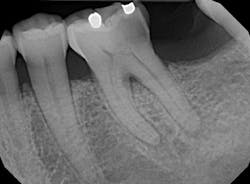

Upon radiographic analysis, noted caries encroaching the pulp chamber, thickening of the PDL on the mesial root, and the start of apical osseous breakdown on the distal root. Pulp chamber and canals deemed slightly constricted and pulp stone recognized towards the distal.